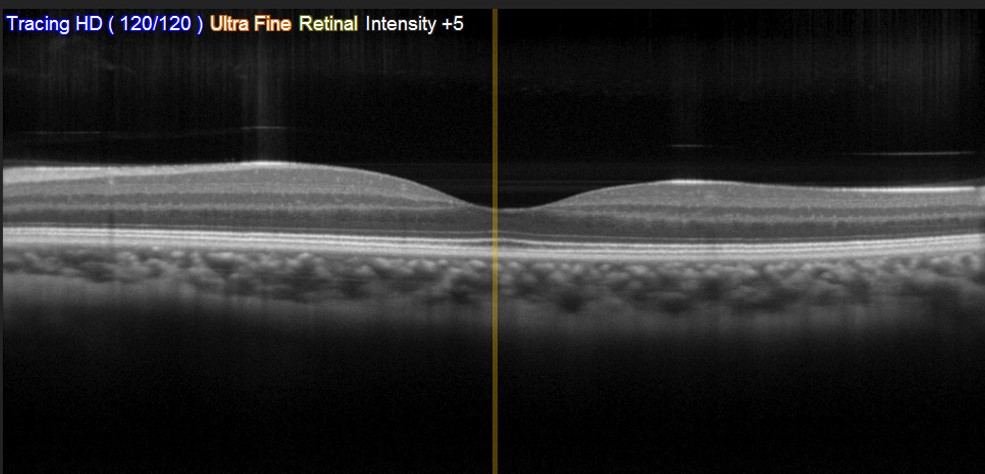

Research has shown genetics can play a role in AMD disease progression. This work aims to use state of the art artificial intelligence software and clinical data including OCT images (like the one shown in the above picture) from large groups of AMD patients to characterise patients into subgroups, to find links between disease progression and genetic risk.